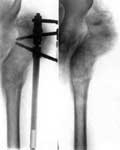

2.Операция Шанца-Илизарова с одновременным удлинением бедра.